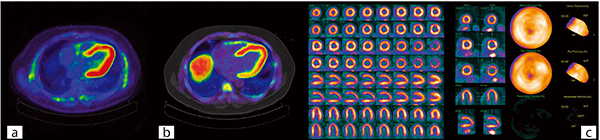

図4 循環器PET検査の一例

18F-FDGの集積(a),13N-ammoniaの集積(b),82Rb-chlorideによるパフュージョン解析の例(c)。